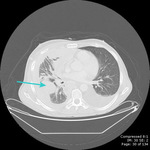

CT scan showing empyema with split pleura sign (enhancement of the thickened inner visceral and outer parietal pleura separated by a collection of pleural fluid)

From the collection of Dr Ami Rubinowitz; used with permission